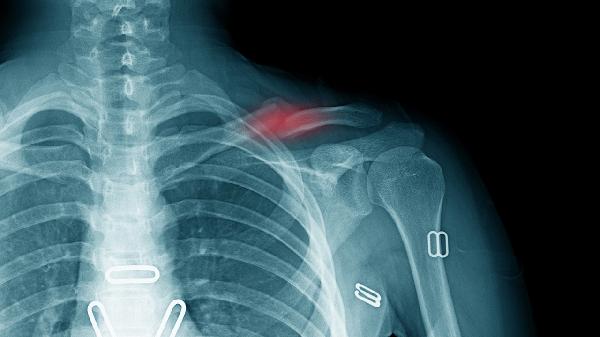

锁骨骨折包括哪些临床表现

锁骨骨折的临床表现主要有局部疼痛肿胀、活动受限、畸形隆起、皮下淤血、骨擦音或骨擦感等。

骨折导致锁骨连续性中断,患者会出现患侧肩关节活动障碍,表现为无法完成上举、外展等动作。部分患者会因疼痛主动限制肩部活动,出现保护性姿势如用健侧手托扶患侧肘部。需通过X线检查明确骨折类型,稳定性骨折可采用八字绷带固定,不稳定性骨折可能需要手术复位。

3、畸形隆起

锁骨位于皮下位置表浅,骨折后由于肌肉牵拉作用,骨折端可能出现明显移位,在体表可见异常隆起或凹陷畸形。中段骨折常见近端向上移位,远端向下移位。儿童青枝骨折可能仅表现为轻微成角畸形。明确诊断后需及时复位固定,避免畸形愈合影响肩关节功能。